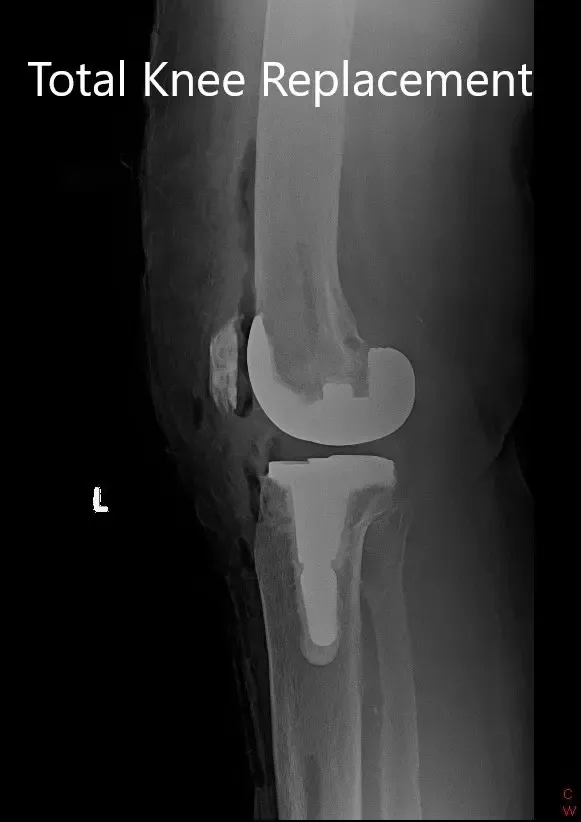

OPERACIÓN: Artroplastia total de rodilla izquierda.

IMPLANTES UTILIZADOS: rótula totalmente poli de 52 mm con fémur tamaño 6 y tibia tallada tamaño E con extensión de tallo de 14 mm.

Radiografía postoperatoria que muestra la articulación de la rodilla izquierda con prótesis en vistas anteroposterior y lateral